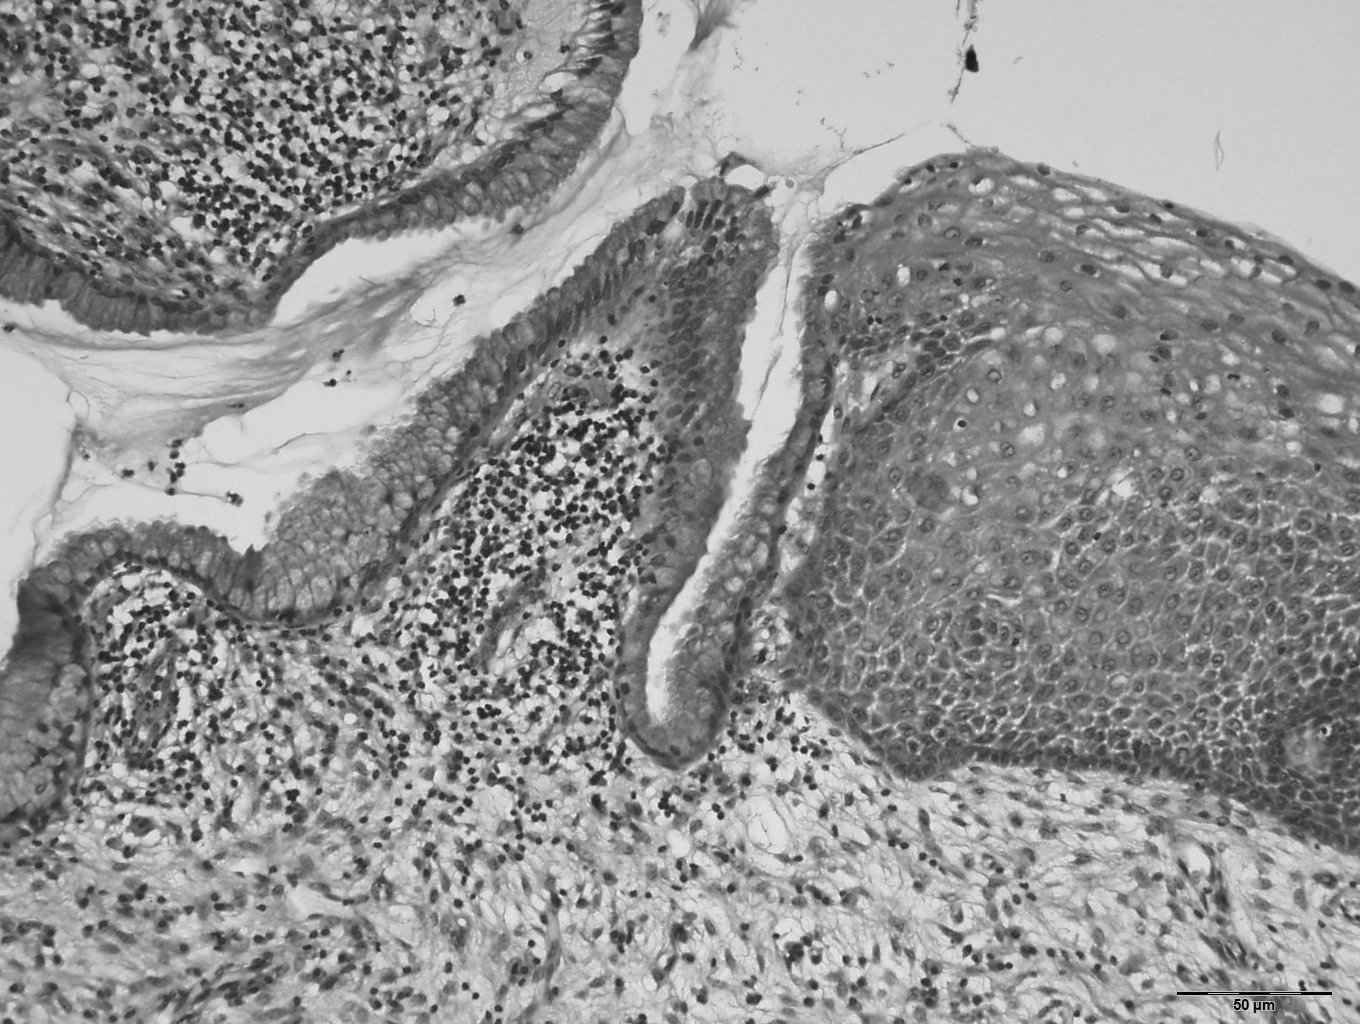

La muqueuse exocervicale (malpighienne) se prolonge dans le canal endocervical par un revêtement cylindrique mucosécrétant accompagné des cellules de réserves (cellules basales de régénération, bipotentes, capables d’une différenciation aussi bien malpighienne que glandulaire) (figure 18.1).

Figure 18.1 Coupe histologique de la jonction squamo-cylindrique normale du col (coloration à l’hématoxyline-éosine et grossissement × 200)

Figure 18.1 Coupe histologique de la jonction squamo-cylindrique normale du col (coloration à l’hématoxyline-éosine et grossissement × 200).